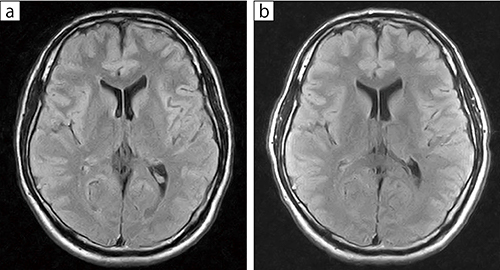

■症例2:関節コイルによる頭部撮像

40歳代,男性。関節コイル(b)を用いても,頭部コイル(a)と比べ遜色ない画質が再現できた。

a:頭部コイル b:関節コイル

FLAIR,TR/TE:9000/112,スライス厚:7mm,FOV:220 mm,FA:90°,マトリックス512×512,撮像時間:3:55